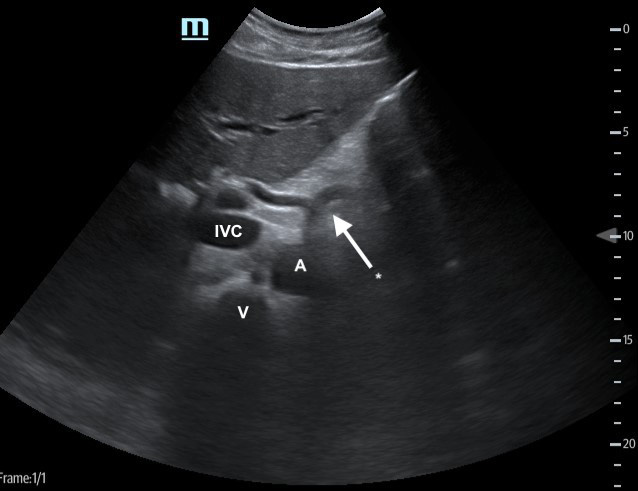

- With the transducer in the subxyphoid region, transducer in the transverse plane, evaluate the periaortic region for large lymph nodes. (Figure 1, #2)

- Identify the arch of the vertebral body in the far field then the aorta just to the patient’s left.

- Identify the “seagull sign” of the celiac trunk and slide the transducer inferiorly to the bifurcation of the common iliac arteries.

- Normally, lymph nodes will be difficult to visualize because they are small and normally hypoechoic with a hyperechoic central hilum. As they enlarge, the architecture is distorted, and they develop a homogeneous echotexture. Attempt to image lymph nodes in 2 planes and measure the diameter.

Figure 3. Proximal aorta (A) with celiac trunk "seagull sign" (*) adjacent to the IVC and vertebral body (V)